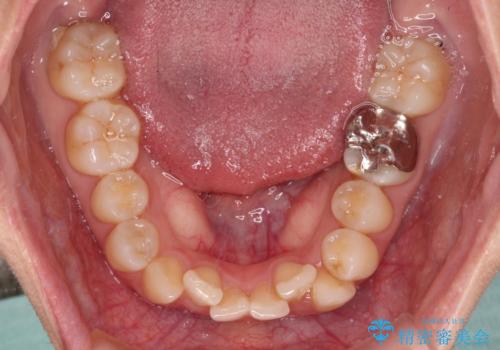

- 上下のクロスバイトと前歯のデコボコを気にして来院された患者様です。

インビザラインを用い、IPR(歯と歯の間を削る)と歯列全体を拡大させることで、歯並びを整えていくこととしました。

下の歯が隠れてしまうほどでしたが、深い咬み合わせも改善され、顎への負担も軽減されました。